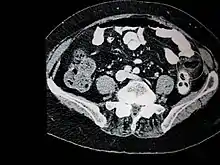

Ultrasound and CT scans are the normal means of positive diagnosis of Epiploic Appendagitis. Ultrasound scans show "an oval, non-compressible hyperechoic mass with a subtle hypoechoic rim directly under the site of maximum tenderness".[4] Normally, epiploic appendages cannot be seen on CT scan.[4] After cross-sectional imaging and the increased use of abdominal CT for evaluating lower abdominal pain, EA is increasingly diagnosed. Pathognomonic CT scan data represent EA as 2–4 cm, oval shaped, fat density lesions, surrounded by inflammation. Contrasting with diverticulitis findings, the colonic wall is mostly unchanged.